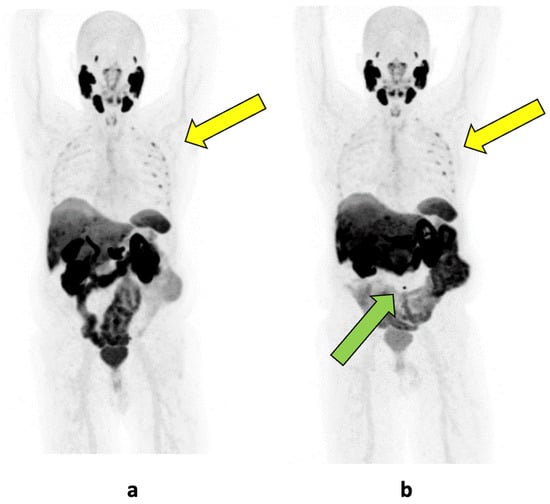

- Shagera, Q.A.; Karfis, I.; Kristanto, P.; Spyridon, S.; Diamand, R.; Santapau, A.; Peltier, A.; Roumeguère, T.; Flamen, P.; Artigas, C. PSMA PET/CT for Response Assessment and Overall Survival Prediction in Patients with Metastatic Castration-Resistant Prostate Cancer Treated with Androgen Receptor Pathway Inhibitors. J. Nucl. Med. 2023, 64, 1869–1875. [Google Scholar] [CrossRef] [PubMed]

- Aggarwal, R.; Wei, X.; Kim, W.; Small, E.J.; Ryan, C.J.; Carroll, P.; Cooperberg, M.; Evans, M.J.; Hope, T.; Aggarwal, R.; et al. Heterogeneous Flare in Prostate-specific Membrane Antigen Positron Emission Tomography Tracer Uptake with Initiation of Androgen Pathway Blockade in Metastatic Prostate Cancer. Eur. Urol. Oncol. 2018, 1, 78–82. [Google Scholar] [CrossRef] [PubMed]

- Barbato, F.; Fendler, W.P.; Rauscher, I.; Herrmann, K.; Wetter, A.; Ferdinandus, J.; Seifert, R.; Nader, M.; Rahbar, K.; Hadaschik, B.; et al. PSMA PET for the assessment of metastatic hormone-sensitive prostate cancer volume of disease. J. Nucl. Med. 2021, 62, 1747–1750. [Google Scholar] [CrossRef] [PubMed]